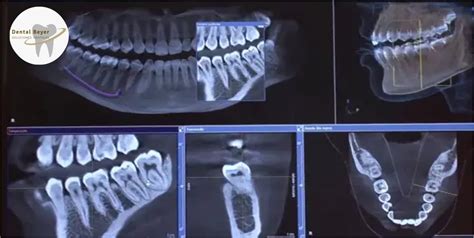

En la Odontología actual, los exámenes radiográficos desempeñan un papel vital en el diagnóstico y seguimiento de las enfermedades orales. Los exámenes radiográficos dentales -como los exámenes panorámicos, cefalométricos y la tomografía computarizada de haz cónico- son necesarios de manera habitual, cuando no diaria, en toda clínica dental.

En los últimos años se van imponiendo los estudios con técnicas digitales: desde los pequeños captadores intraorales CDC, con su cable conectado al digitalizador, o los de fluorescencia que precisan de un «revelado», hasta los más modernos aparatos de tomografía 3D han venido a ayudarnos a cumplir con parte de los requisitos de protección, ya que estas exploraciones permiten realizar las radiografías en un menor tiempo y con una dosis de radiación menor, hasta un 90% de una exploración tradicional.

En una exploración tomográfica con la técnica de haz de cono (Cone Beam CT, del inglés) la reducción de la dosis efectiva recibida por el paciente es de hasta el 90% en comparación con un escáner médico convencional.

No se encontró artículos que evaluaran el conocimiento de las especificaciones técnicas de la tomografía computarizada de haz cónico (TCHC) en relación con la PRO. Esta situación es preocupante, debido al amplio uso de la TCHC y a que las dosis de radiación emitidas por equipos de TCHC son generalmente más altas que las emitidas por los equipos de rayos X bidimensionales (2, 21).